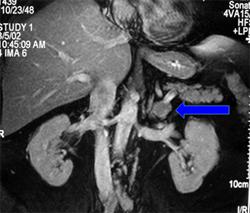

- Tomografia komputerowa (CT): Pozwala na dokładne określenie lokalizacji, rozmiaru oraz cech morfologicznych guza, co umożliwia przeprowadzenie oceny przedoperacyjnej i monitorowanie zmian w czasie.

- Rezonans magnetyczny (MRI): Zapewnia szczegółowe obrazy strukturalne guza i otaczających tkanek, co może być przydatne w planowaniu operacji chirurgicznej oraz ocenie potencjalnego zaangażowania okolicznych struktur.